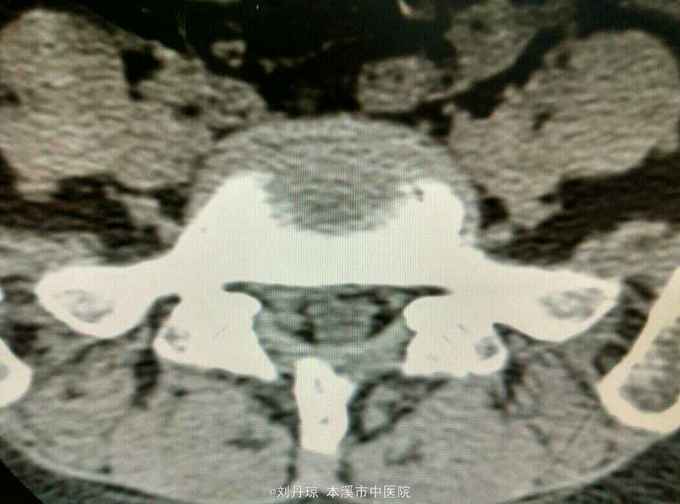

腰痛伴有右下肢放射痛三年,加重十天。患者三年前因抬重物腰部刺痛,休息一周后好转,十天前因开车劳累4.5小时后又洗澡,第2天即感右下肢放射痛难以忍受,遂由门诊收入院治疗。

查体:L5—S1棘突旁压痛阳性。直腿抬高实验。左70度,右30度。加强试验左侧阴性,右侧阳性。腰椎功能障碍。CT:L5—S1椎间盘突出。